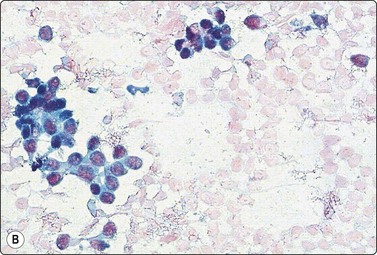

A comparison between the basic benign pattern (non-neoplastic glandular tissue) and the most common malignant pattern (low-grade carcinoma of no special type) in FNB of breast lesions is given in Table 7.2 (Figs 7.2-7.4).

Non-neoplastic breast tissue (Figs 7.2A, 7.3A and 7.4A) Low-grade carcinoma NOS (Figs 7.2B, 7.3B and 7.4B)

1. Overall low cell yield 1. Variable but higher cell yield

2. Sheets and aggregates of cohesive, small, uniform cells 2. Irregular clusters of less cohesive, small, mildly irregular cells

3. Small rounded nuclei, bland chromatin, some overlapping 3. Slightly larger and darker nuclei, relatively bland chromatin

4. Myoepithelial cell nuclei among epithelial cells 4. Myoepithelial cell nuclei not seen

5. Variable numbers of single, bare, bipolar nuclei scattered in the background 5. Single cells, most with some cytoplasm, identical to those forming clusters; no bare bipolar nuclei

image image

Fig. 7.2 Non-neoplastic glandular breast tissue and low-grade duct carcinoma

Low-power view; (A) Bimodal population of epithelial sheets and single bipolar nuclei of non-neoplastic glandular breast tissue; (B) Single population of epithelial cells in low-grade carcinoma (MGG, LP).

Fig. 7.3 Non-neoplastic glandular breast tissue and low-grade duct carcinoma

High-power view, air-dried smears; (A) Non-neoplastic glandular breast tissue; (B) Low-grade duct carcinoma. Note single bipolar nuclei in A, and absence of bipolar nuclei, relatively mild nuclear atypia and some loss of cohesion of malignant cells in B (MGG, HP).

Fig. 7.4 Non-neoplastic glandular breast tissue and low-grade duct carcinoma

High-power view, Pap-stained smears; (A) Bimodal population in smear from non-neoplastic breast; (B) Single and clustered cells in low-grade carcinoma; some single cells probably stromal (Pap, HP).